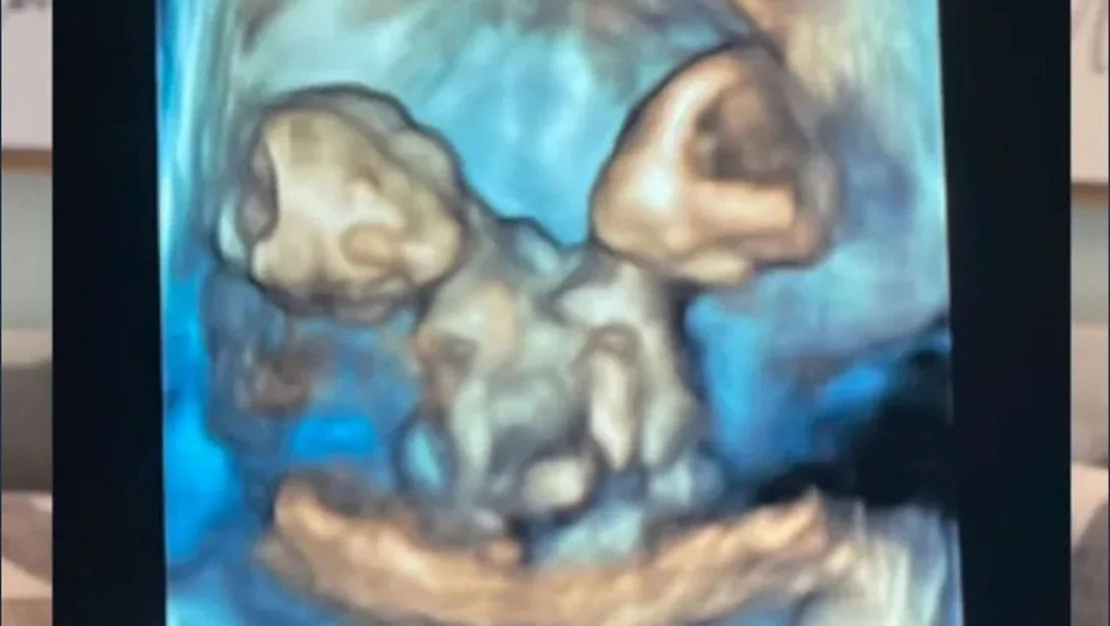

ABD’nin Michigan eyaletinde yaşayan Nicole ve Austin LeBlanc çifti, ilk defa bebek sahibi olmanın heyecanını yaşadı. Ancak, bu mutlulukları uzun sürmedi. Gebeliğin yedinci haftasında yapılan muayenede ultrasonda yalnızca bir kalp atışı duyulmasına rağmen ikiz gebelik olabileceği ihtimali gündeme geldi. Kısa bir süre sonra, Nicole şiddetli karın ağrılarıyla hastaneye kaldırıldığında gerçek ortaya çıktı. Anne adayı, aynı kalbi, karaciğeri, bağırsakları, diyaframı ve göbek kordonunu paylaşan ikiz kız bebeklere hamileydi.

Nicole, 32. haftada sezaryenle ikizlerini dünyaya getirdi. Maria Therese ve Rachel Clare adını verdikleri bebekler, doğum anında farklı tepkiler verdi. “Maria yüksek sesle ağladı, Rachel ise uyuyordu. Yüzlerini görmek ve paylaştıkları bedene şahit olmak inanılmazdı” diyerek o duygusal anları gözyaşları içinde anlattı. Ancak ne yazık ki, ikizler, doğumdan çok kısa bir süre sonra anne ve babalarının kucağında hayata gözlerini yumdu.